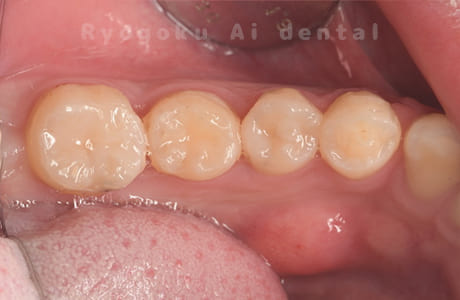

-

歯牙移植咬合面術前 -

移植する親知らず

歯牙移植術直後咬合面

歯牙移植術後咬合面

歯牙移植術前側面

歯牙移植術中側面

歯牙移植術後側面

部分矯正術前咬合面

部分矯正術中咬合面

部分矯正術後咬合面

部分矯正術前側面

部分矯正術中側面

部分矯正術後側面

- 原因

- 重度カリエス

- 治療内容

- 自家歯牙移植、部分矯正

- 治療費用

- 220,000円(移植費用)

110,000円(部分矯正費用)

虫歯が大きく、保存不可能となった歯を上の親知らずと交換する自家歯牙移植を行いました。移植歯が小ぶりであったため、部分矯正を行い問題なく噛み合い、経過良好です。